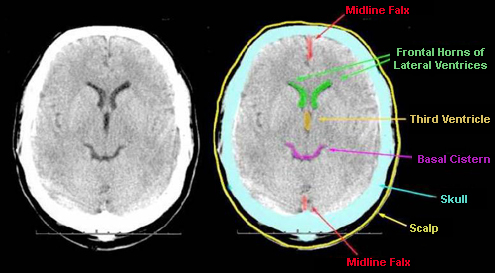

The Mind Project's Virtual Stroke Lab EMR Entry - Reading CT Scans